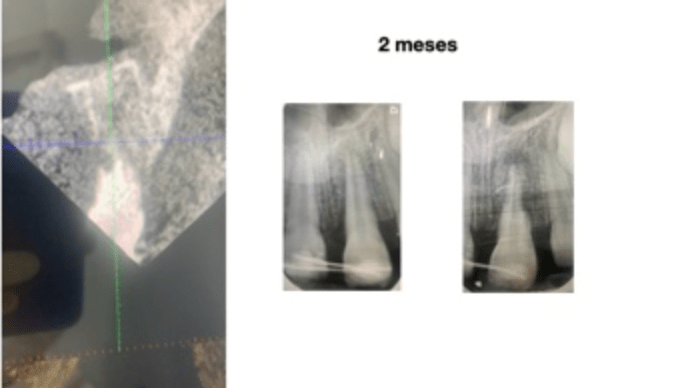

Casos con curación

Gran lesion algaba 6 meses